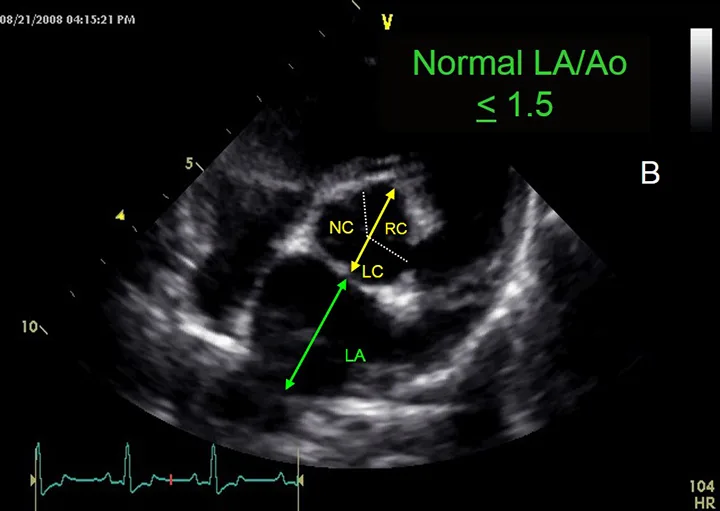

Labeled M-mode echocardiogram demonstrating measurements of features of the left ventricle.

FIGURE 3A

Left ventricular measurements using M-mode echocardiography. During both systole and diastole, this image demonstrates interventricular septum thickness (IVSs, IVSd), left ventricular (LV) internal dimension (LVIDs, LVIDd), and LV free wall thickness (LVWs, LVWd). Increased LVIDd causes left ventricular volume overload, whereas increased LVIDs results in systolic dysfunction.